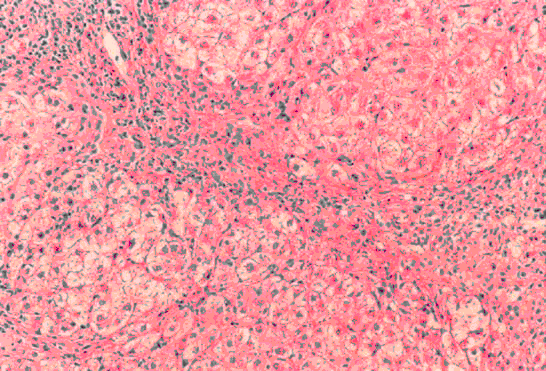

3、单项选择题

患者男,42岁,因“牙龈肿胀2个月”来诊。查体:局部牙龈肿胀,质韧,触之出血。行活检。镜检形态学表现如图所示。

A.弥漫大B细胞淋巴瘤

B.间变大细胞淋巴瘤

C.淋巴母细胞淋巴瘤

D.急性髓系白血病浸润

E.低分化癌浸润

F.恶性黑色素瘤